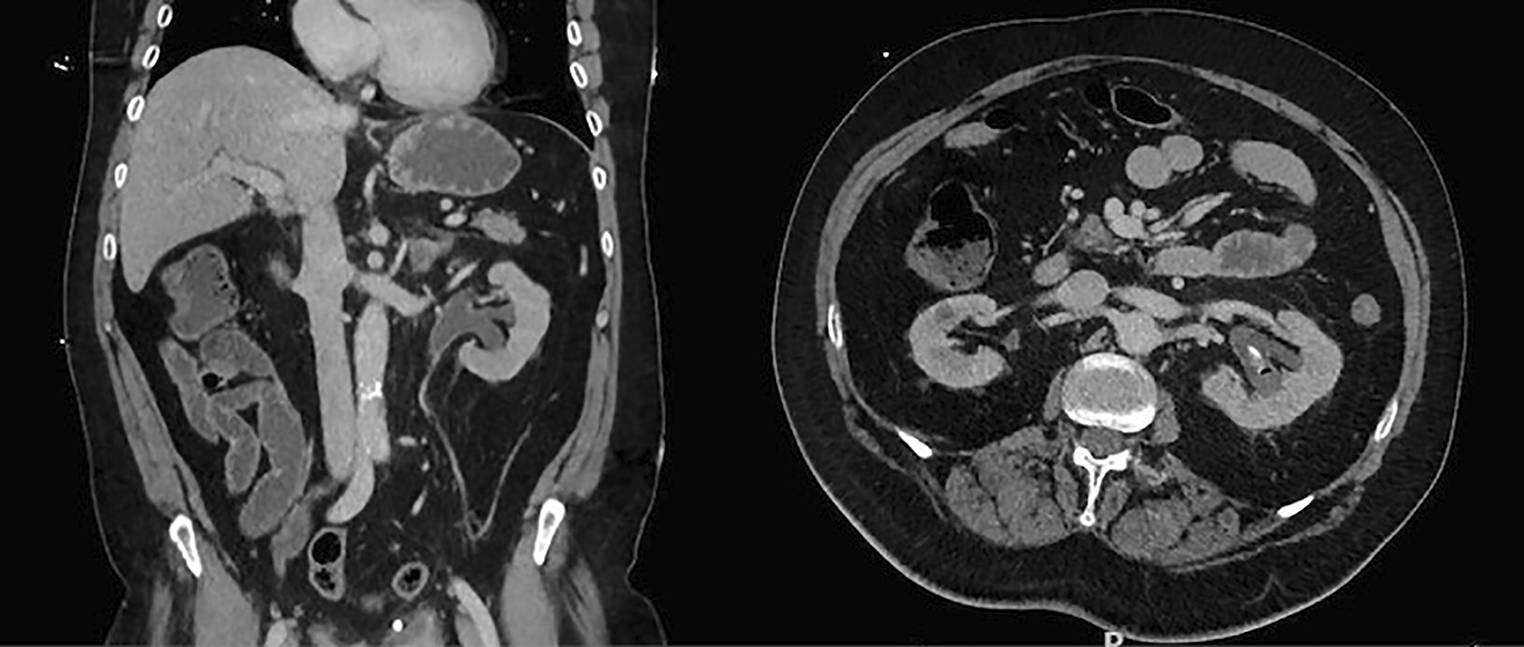

Enkele weken later presenteerde de patiënt zich opnieuw met urosepsis bij een slecht aflopende TUC, zonder problemen met de NSK. Op CT-blanco (fig. 2) werd een toename van luchtconfiguratie in het pyelum links waargenomen. De patiënt werd heropgenomen voor intraveneuze antibiotische behandeling. Op basis van de urinekweek, waaruit onder andere een extended spectrum beta-lactamases (ESBL) Escherichia coli kwam, werd de patiënt uitbehandeld met ciprofloxacine gecombineerd met fluconazol.

Figuur 2

CT-blanco: toename van luchtconfiguratie in het linker pyelum

De behandeling leverde wisselende resultaten op (fig. 3), maar bij evaluatie na negen weken intrapyelische spoelingen bleek er een beduidende toename te zijn en werd besloten dat er sprake was van onvoldoende broncontrole. Er werd een nieuwe evaluatie van disseminatie uitgevoerd met FDG-PET/CT, fundoscopie en een transoesofageaal echocardiogram, die geen strooihaarden aantoonde. Bijgevolg werd besloten tot operatief ingrijpen om de fungal balls te verwijderen. De spoelingen werden tot aan de operatie nog vervangen door anidulafungine (50 mg/l). Vierentwintig uur preoperatief werd meropenem en caspofungine gestart ter dekking van respectievelijk eerdere ESBL en Candida albicans. De fungal balls konden volledig en succesvol worden verwijderd met robotgeassisteerde pyelo- en cystotomie (fig. 4).